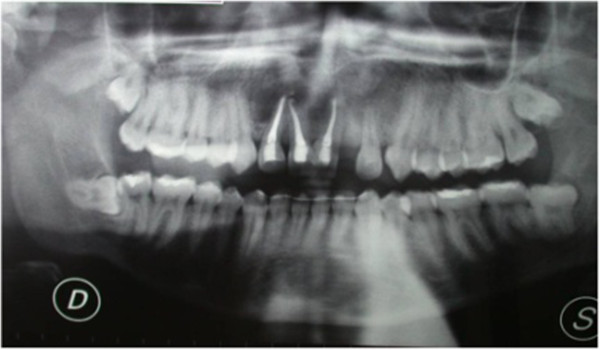

Vitality pulp tests were negative for central incisors and right lateral incisor. A radiographic investigation showed a fused tooth with separate pulp chambers, two distinct roots and two separate root canals associated with periapical lesions of central incisors and right lateral incisor (Figure 2). A presumptive diagnosis of a radicular inflammatory cyst was made.

Figure 2.

Panoramic radiographic.

After six months, a radiographic control revealed the persistence of periapical radiolucency (Figure 3). We then decided to perform endodontic surgery, which included exeresis of the lesions (Figure 4), apicoectomy, and retrograde obturation with a reinforced zinc oxide-eugenol cement (SuperEBA).

Figure 3.

Persistence of periapical radiolucency at six months control.